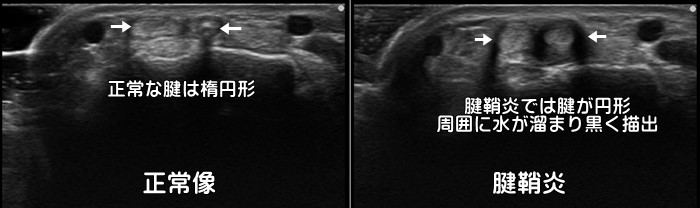

指の腱鞘炎・ばね指

正常な腱は楕円形ですが、炎症を起こした腱は肥大し円形になります。また腱周囲の腱鞘に水が溜まり黒く描出されます。発症頻度は第1→3→4指の順です。腱が肥大するとプローブからの超音波が乱反射してうまく返ってこない為に一部が黒く描出されるdark

tendon signが見られます。※tendon=腱